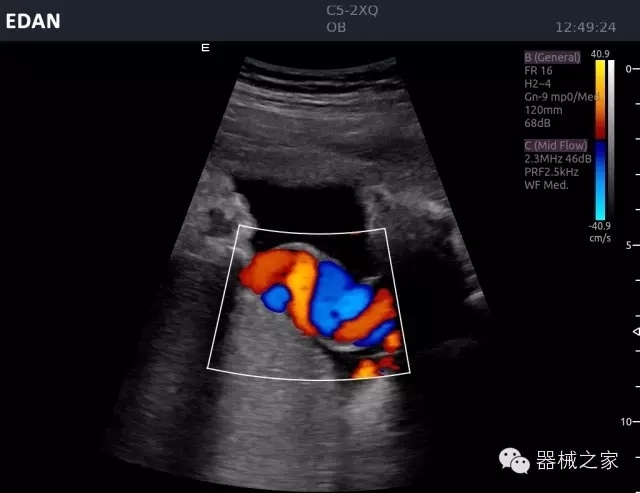

臍帶血流